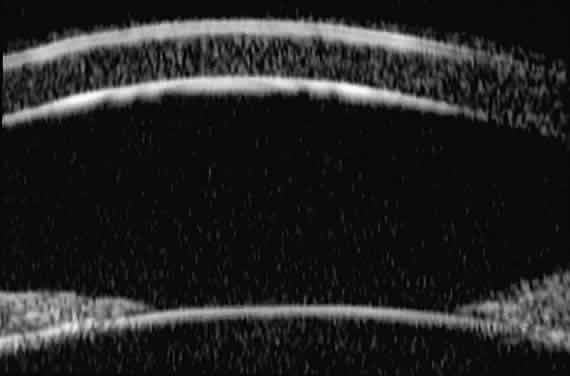

Ultrasound biomicroscopic slices through the mid-cornea and pupil (Fig. 3) show (1) the cornea, (2) the anterior chamber, (3) the lens, and (4) the pupillary zone of the iris. The cornea appears to have four well-differentiated layers. The epithelium is a thin, relatively bright (sonoreflective) layer. Just below that is Bowman's membrane, which appears as a highly reflective, very bright line. The stroma is the thickest layer and shows relatively homogeneous low-amplitude reflectivity. The endothelium and Descemet's membrane cannot be differentiated; together they form a single, highly reflective line at the posterior corneal surface. The aqueous in the normal anterior chamber appears completely sonolucent. The pupillary zone of the iris appears as two fingerlike structures consisting of a relatively sonolucent stroma and a bright posterior pigment epithelium. The anterior lens capsule appears as a bright retropupillary line. The normal anterior lens cortex appears nearly sonolucent.1–3

Fig. 3. UBM slice through mid-cornea and pupil of normal eye.